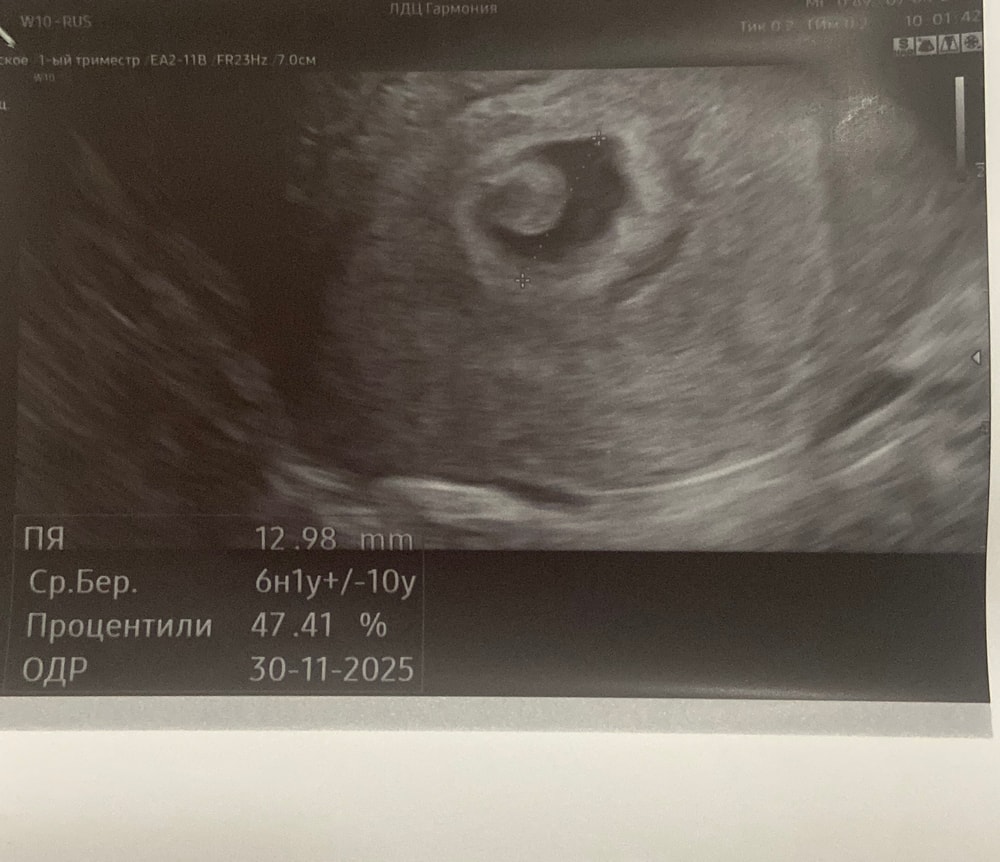

сегодня 7 апреля пошла на первое узи для подтверждения. Сказали 6 недель со дня последний менструации. В мешочке увидели пока что только колечко. И написали что эмбрион не визуализируется. Ходила в клинику платно, толком ничего не объяснили, 11 апреля пойду в другую клинику еще раз сделаю узи, и вечером к гинекологу.

фото хгч и узи прикладываю.

Марина, овуляция была 13 марта. Получается 3 недели и 5 дней прошло. На 5-ый день было узи вчера

Диана Ноилес, получается вчера было 25 дпо,это рано для эмбриона,не переживайте,я выше динамику свою скинула в удачную беременность,на 31 дпо эмбрион 5 мм был,если взять что он растет 1 мм в сутки,то он появился только на 26 дпо и размером 1 мм и такой размер аппарат УЗИ не видет,вас очень рано выводы делать,УЗИ через неделю

Гиперэхогенный желточный мешок это плохо. Плюс он большой. Это тоже плохо.

Мешочек странный, но может это узи такое 🤷🏼♀️ в любом случае сделать узи в динамике - уже хоть что-то должно будет появится

Недельку подождите, и на УЗИ))) ПЯ у вас ещё не большое, недель на 5, может позднее была овуляция или имплонтация)))